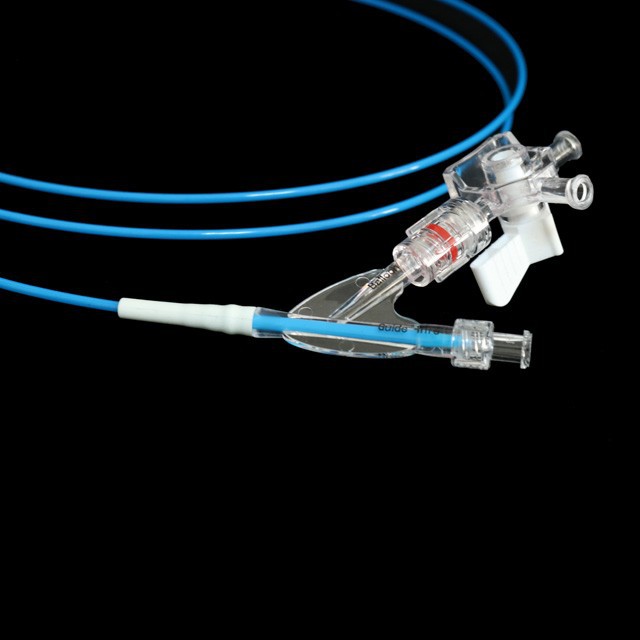

● elastica mollis consilium consilium, quod potest aequaliter intrare in scopum positus cum minus damnum .

● thermostatic shaping post multi-Wing Tueing confert ad optimum mollitiam et flexibilia receptum a working channel {I}}

● optimal consilio fistulam facit eam lenis et boni elasticitate, fortis torquens resistentia et facilius passability .

● Pre-input 0 {{II}} XXXV "Guide filum cum mollis tip et marcam, quae est facillimus estimate longitudinem in medio Guide filum.